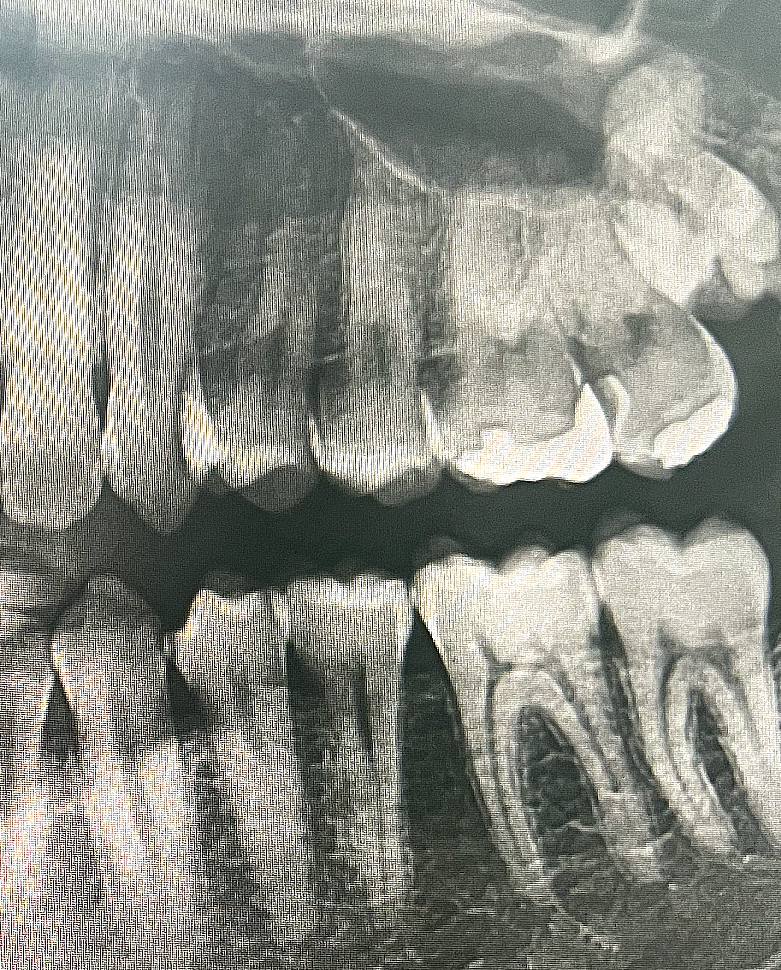

엑스레이 및 구강사진으로 충치진단

어떤 치아를 어떤 치료해야할지 알려주세요

• 1번 째 사진

치아 사이에 즉, 인접면 충치가 다수 있으신거 같습니다. 저정도면 진행되는 충치이니 치료를 하시는게 좋을것같습니다.